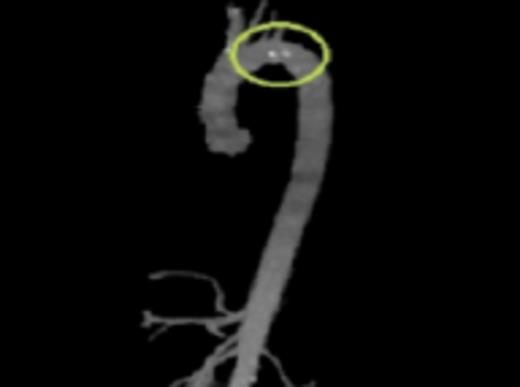

CTA reconstruction highlighting the floating plaques distal to the Left Subclavian artery takeoff

Initial workup included a transesophageal echocardiogram (TEE) which showed a 0.8cm × 0.9cm highly mobile plaque just distal to the take-off of the left subclavian artery. CT angiography (CTA) was then performed to further delineate the anatomy and to evaluate for the possibility of endovascular stent graft placement. CTA showed a thoracic aortic intraluminal filling defect which represented a small area of clot within an atherosclerotic plaque. The CTA also demonstrated an area of decreased attenuation on the upper anterior portion of the spleen consistent with an older splenic infarct.